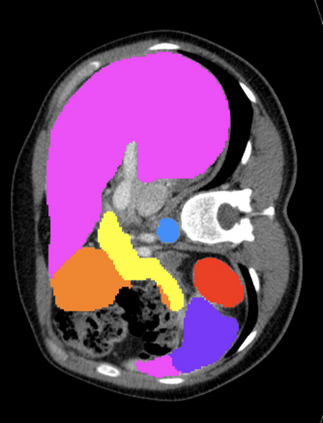

Most recent semantic segmentation methods adopt a U-Net framework with an encoder-decoder architecture. It is still challenging for U-Net with a simple skip connection scheme to model the global multi-scale context: 1) Not each skip connection setting is effective due to the issue of incompatible feature sets of encoder and decoder stage, even some skip connection negatively influence the segmentation performance; 2) The original U-Net is worse than the one without any skip connection on some datasets. Based on our findings, we propose a new segmentation framework, named UCTransNet (with a proposed CTrans module in U-Net), from the channel perspective with attention mechanism. Specifically, the CTrans module is an alternate of the U-Net skip connections, which consists of a sub-module to conduct the multi-scale Channel Cross fusion with Transformer (named CCT) and a sub-module Channel-wise Cross-Attention (named CCA) to guide the fused multi-scale channel-wise information to effectively connect to the decoder features for eliminating the ambiguity. Hence, the proposed connection consisting of the CCT and CCA is able to replace the original skip connection to solve the semantic gaps for an accurate automatic medical image segmentation. The experimental results suggest that our UCTransNet produces more precise segmentation performance and achieves consistent improvements over the state-of-the-art for semantic segmentation across different datasets and conventional architectures involving transformer or U-shaped framework. Code: https://github.com/McGregorWwww/UCTransNet.